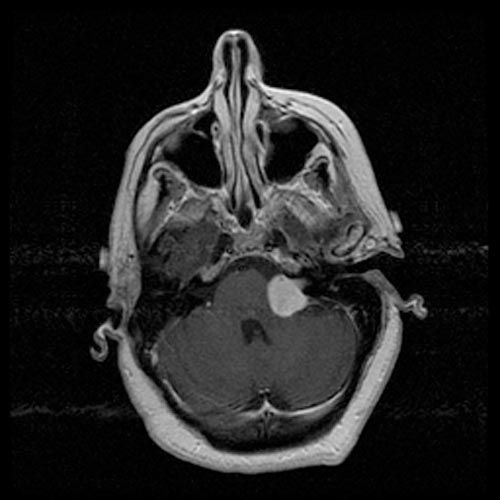

Skull base MDT Referral Form

Vestibular Schwannoma Management Protocol